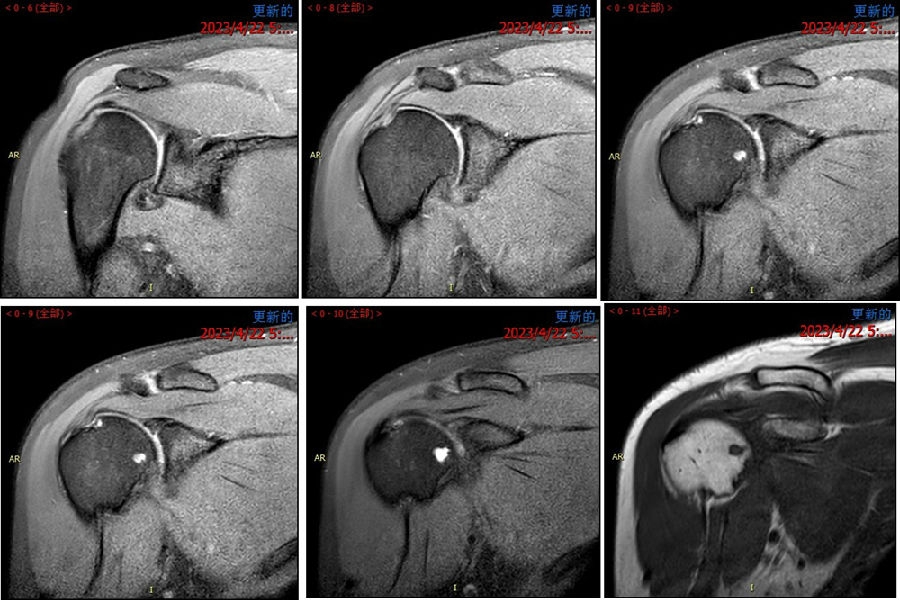

图 25-27 MRI

图39 此次复发脱位MR评估

图44 术前MRI